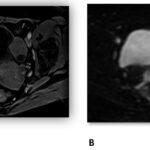

Se presenta el caso de una paciente de 56 años, posmenopáusica, con antecedente de Ca mama en tratamiento con anastrozol, anexectomía derecha por cistoadenoma seroso. Consulta por sangrado uterino anormal de un mes de evolución. Se realizan exámenes complementarios, como ecografía transvaginal y resonancia magnética pélvica, para evaluar la lesión; se categorizó como ORADS IV.

El artículo concluye resaltando la importancia de considerar a la ecografía como el primer método diagnóstico, y con la RMN de pelvis se estratifica el riesgo de malignidad. Sin embargo, su confirmación diagnóstica concluye con el resultado anatomopatológico posquirúrgico en la mayoría de los casos.

Se presenta el caso de una paciente de 56 años, posmenopáusica, con antecedente de Ca mama en tratamiento con anastrozol, anexectomía derecha por cistoadenoma seroso. Consulta por sangrado uterino anormal de un mes de evolución. Se realizan exámenes complementarios, como ecografía transvaginal y resonancia magnética pélvica, para evaluar la lesión; se categorizó como ORADS IV.

Resaltamos la importancia de considerar a la ecografía como el primer método diagnóstico, y con la RMN pelvis se estratifica el riesgo de malignidad. Sin embargo, su confirmación diagnóstica concluye con el resultado anatomopatológico posquirúrgico en la mayoría de los casos.

Anexos (imágenes)